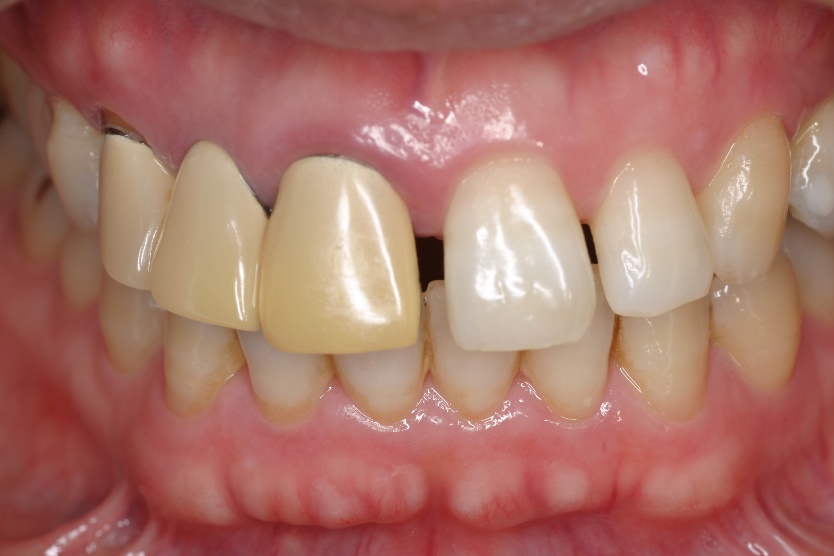

セラミッククラウンとコンポジットレジンによる審美修復治療をおこないました。

治療後

エックス線検査ではしっかりあってます。

歯肉圧排は省略しても患者さんにはわかりません。むしろやらない方が早く簡単に終わるので患者さんには喜ばれるかもしれません。しかしいくら材料が良くてもこの行程が無ければ、境目にプラークが簡単に溜まり虫歯や歯周病が再発します。審美修復治療の違いは材料だと説明される事が多いようですが、私はどのようなテクニックが使われるかだと思います。